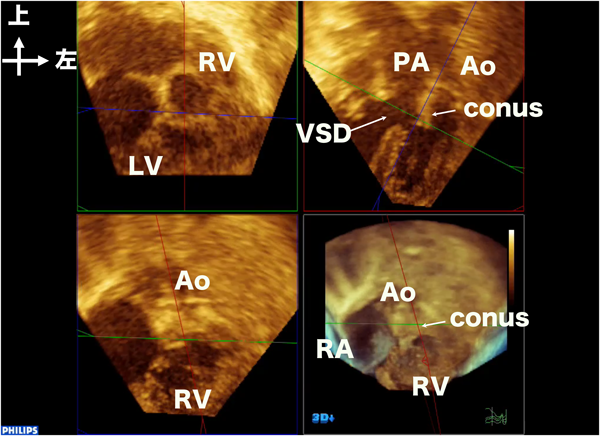

2025年最新】周術期経食道心エコー 連問式症例問題集の人気。周術期経食道心エコー 連問式症例問題集 | 春日 武史 |本 | 通販。2025年最新】周術期経食道心エコー 連問式症例問題集の人気。にゃんころ☆ぼっち立て天日干しコシヒカリ中身5kg以上おまけつき。心エコーによる僧帽弁狭窄の重症度評価と問題点 | 「心臓」特別。3D心エコー:どうやって使えば手術に役立てられるか? 解剖学的。3D/4Dエコーの応用|千葉県の北森ペット病院。うし先生@Hiroki Uehara | 日本周術期経食道心エコー(JB-POT)の。心エコー|Gajumaruのメディカルワークアウト。108A57 | 僧帽弁閉鎖不全症 国試 | M3E Medical。裁断済みのため状態が悪いとしていますが、書込み等一切なくきれいな状態です。周術期経食道心エコー 連問式症例問題集 | 春日 武史 |本 | 通販。動画視聴コードは使用済みですので、コード記載のページを抜かせていただきます。医学界新聞プラス [第1回]心エコーレポートの見方をざっくり。ご理解いただける方のみご購入をお願いいたします。解きながらレベルアップ|真興交易株式会社。「周術期経食道心エコー 連問式症例問題集」春日 武史定価: ¥ 12000#春日武史 #春日_武史 #本 #自然/医療・薬学・健康 #jbpot #心臓血管外科 #循環器内科